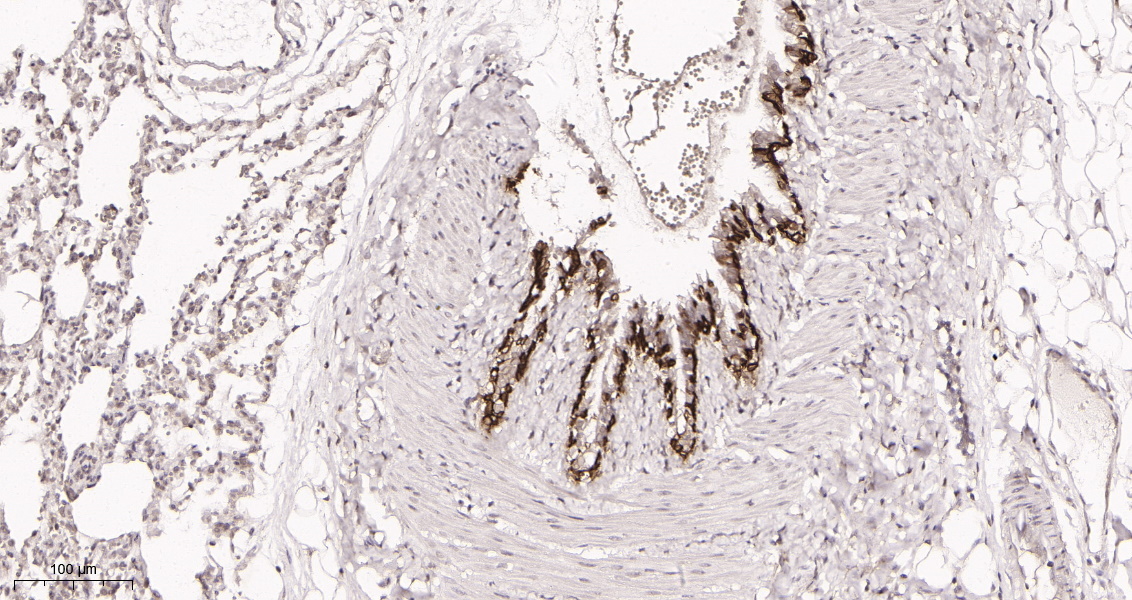

产品名称Cytokeratin 5 (10X11) Rabbit Monoclonal Antibody

推荐应用WB,IHC-P,IF-P,IF-F,IF-ICC,ELISA

稀释度IHC-P 1:200-1:1000, WB 1:1000-1:5000, IF-P/IF-F/IF-ICC 1:200-1:1000, ELISA 1:5000-1:20000

背景介绍keratin 5(KRT5) Homo sapiens The protein encoded by this gene is a member of the keratin gene family. The type II cytokeratins consist of basic or neutral proteins which are arranged in pairs of heterotypic keratin chains coexpressed during differentiation of simple and stratified epithelial tissues. This type II cytokeratin is specifically expressed in the basal layer of the epidermis with family member KRT14. Mutations in these genes have been associated with a complex of diseases termed epidermolysis bullosa simplex. The type II cytokeratins are clustered in a region of chromosome 12q12-q13. [provided by RefSeq, Jul 2008],